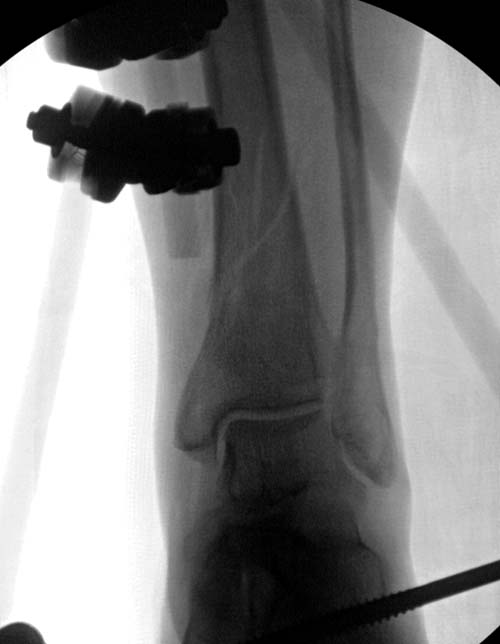

Второй случай в результате скоростной травмы, кроме пилона, вовлечение

других органов! Отек при поступлении и открытый перелом на другой

стороне. В таких случаях нет смысла спешить, и временный наружный

фиксатор на несколько дней. После спадения отека фиксация

передне-наружной пластиной.  Реабилитация - ранние движения, без

нагрузки.